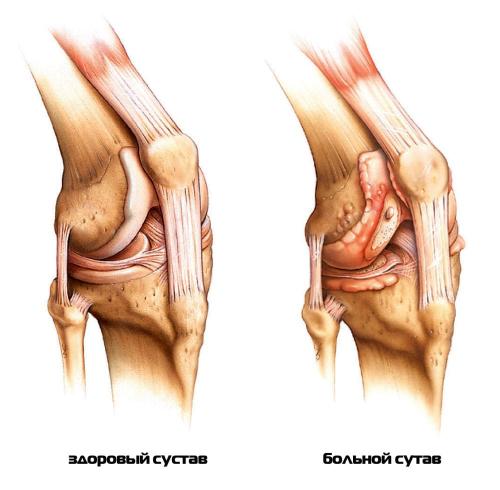

Жжение в коленном суставе появляется на начальном этапе развития любой острой воспалительной патологии. Оно сопровождает все хронические заболевания, возникает на стадии ремиссии и во время рецидивов.может поражать хрящевые, костные, мягкие ткани, мышцы, связочно-сухожильный аппарат. Он бывает первичным, развивающимся в ответ на предшествующую травму, или вторичным, возникающим на фоне деструктивно-дегенеративных изменений в колене. Жжение часто становится одним из первых клинических проявлений следующих воспалительных патологий:

- ревматоидный и реактивный артрит . Основная причина заболевания — нарушение ответа иммунной системы, которая начинает атаковать собственные клетки организма. Воспалением оказываются поражены синовиальные сумки, хрящевые и мягкие ткани. Колено отекает, кожа над суставом краснеет, становится горячей на ощупь;

- бурсит , синовит . Артриты, артрозы, инфекции способны стать причиной воспаления синовиальных сумок с образованием и накоплением в них жидкости — патологического экссудата. Пораженное колено сильно опухает и болит . Помимо жжения, в нем ощущаются боли, усиливающиеся во время ходьбы , сгибания или разгибания сустава .